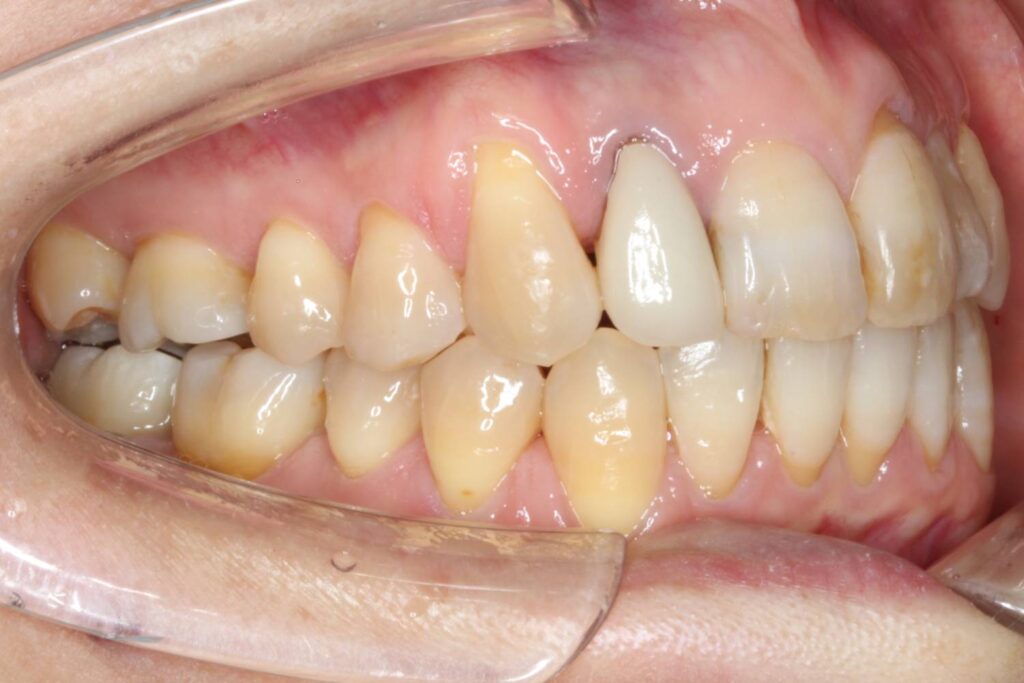

右上の2番目の前歯が完全に内側へ転位しており、1番目の前歯は大きく捻じれている状態です。

それに伴って上顎の歯並びの中心が左側へずれてしまっています。

また、下顎の前歯にもがたつきがあり、左下奥歯はブリッジが入っている状態です。

Before